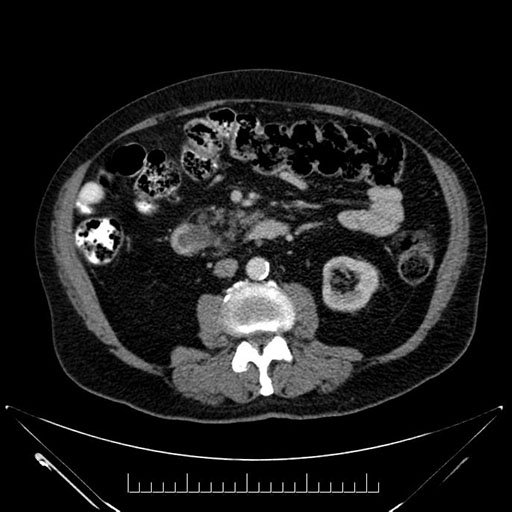

Imaging Analysis

Look through the patient's CT scan to identify any areas of concern for the necessary procedure.

Based on your CT findings, which issue(s) would give reason for "planned slowing down moment(s)" in this case?

Considering a standard Whipple procedure, what step(s) of the operation would you do differently in this case?